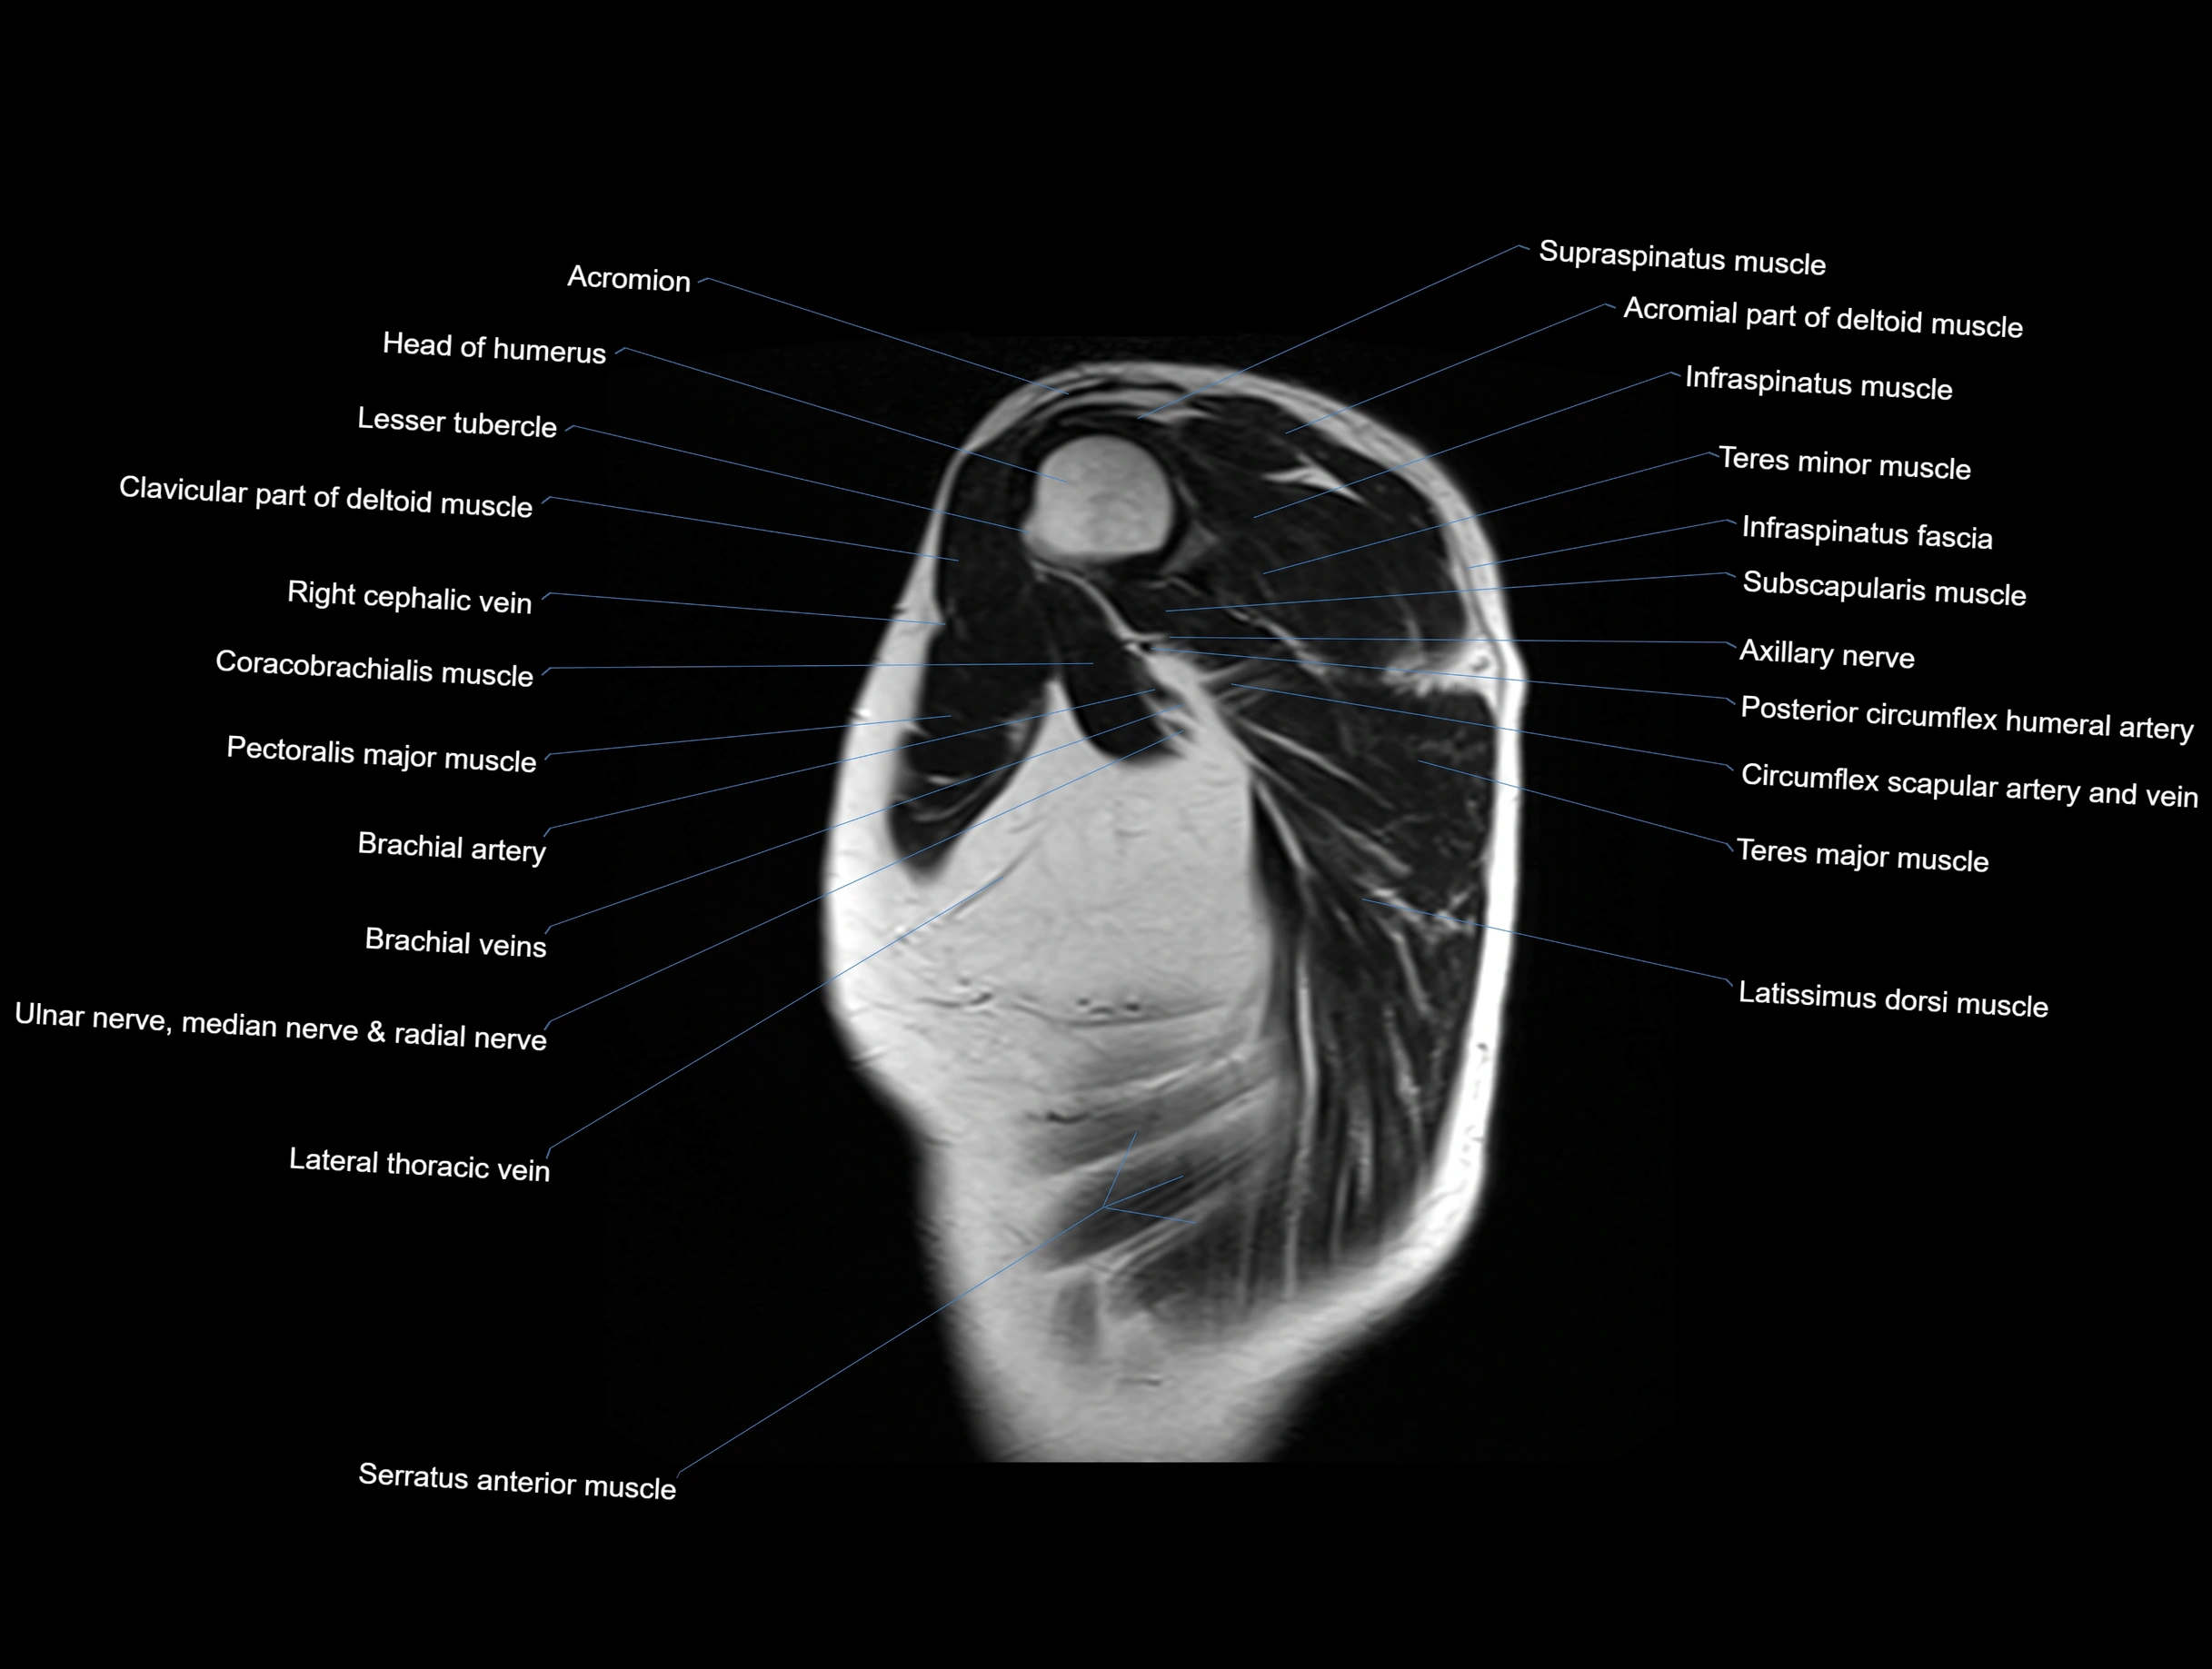

- Axillary nerve

- Biceps brachii muscle

- Cephalic vein

- Clavicular part of deltoid muscle

- Coracobrachialis muscle

- Head of humerus

- Infraspinatus muscle

- Lesser tubercle of humerus

- Long head of biceps brachii muscle

- Pectoralis major muscle

- Posterior circumflex humeral artery

- Subscapularis muscle

- Supraspinatus muscle

- Teres major muscle

- Teres minor muscle